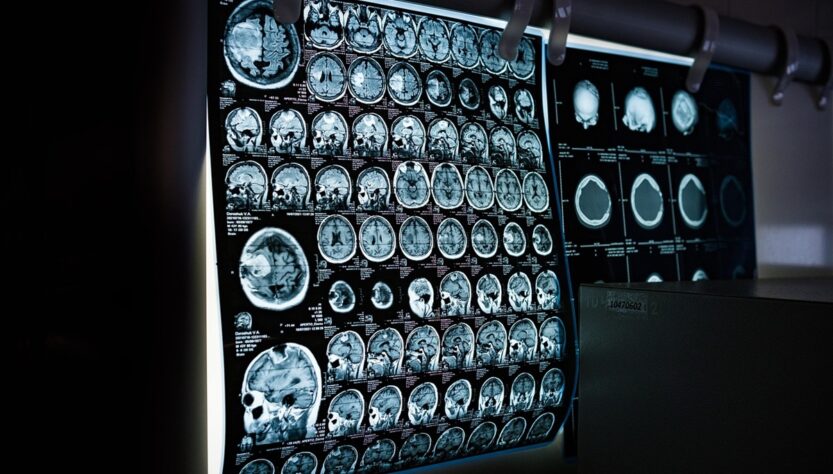

У молодої американки Енні Седорік протягом двох років виявили рідке гормональне захворювання – акромегалію, спричинене пухлиною гіпофіза. Жінка марно шукала причину різкого погіршення здоров’я, включаючи біль, деформації обличчя та проблеми зі здоров’ям. Після численних консультацій та операцій лікарі нарешті поставили правильний діагноз. Після видалення пухлини вона стикалася з ускладненнями, але зараз продовжує боротьбу з хворобою, проходячи регулярні обстеження. Жінка веде активний спосіб життя, але визнає, що життя з невидимою хворобою та постійним болем є великим викликом.